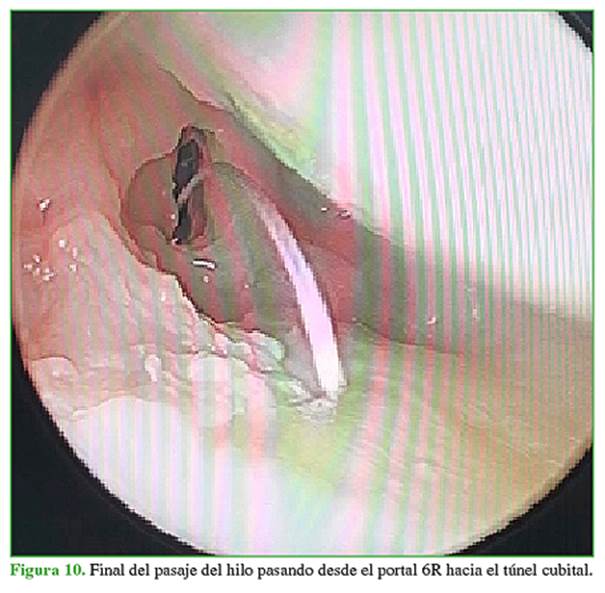

Se procede a la sinovectomía y el desbridamiento de la lesión (Figura 2). A continuación, se coloca la guía del CFCT por el portal 6R y bajo visión ¾, se coloca la guía en la zona 2/2 descrita por Matsumoto (Figura 3). Se efectúa un abordaje cubital de 2 cm para colocar la guía al mismo tiempo que se la posiciona por el portal 6R y se coloca una clavija por la guía hasta salir en la articulación y asegurarse de estar en la zona 2/2. Se fresa con una guía de 3.0 desde el cúbito hasta la articulación. Al finalizar se retira la guía y se coloca por el orificio cubital un pasador de hilo 2.0 tipo fiberwire penetrando el disco; se retira ese hilo por el portal 6R sin perderlo por el túnel cubital (Figuras 4-6). A continuación, se coloca un pasador de hilo con un rescatador de sutura por el túnel cubital penetrando el disco 2 mm a volar o dorsal y se retira el rescatador de sutura por el portal 6R (Figuras 7-9). Se pasa el hilo por el rescatador de sutura y se tira desde el rescatador de sutura por el abordaje cubital siempre mirando desde portal ¾. Se observa cómo la sutura pasa hacia el orificio cubital tensando el fibrocartílago (Figuras 10-12). Mediante un dispositivo de anclaje sin nudo de 2,8 mm se colocan las dos puntas de los hilos dentro del sistema de fijación y se lo impacta 5 mm distal al túnel realizado (Figuras 13 y 14). Se comprueba que las pruebas del trampolín y del gancho sean negativas, se retira la tracción y se prueba la estabilidad. Se cierran los portales. Se coloca una férula tipo Munster (pinza de azúcar) por cuatro semanas con movilidad de dedos y hombro, y luego, se inicia el programa de rehabilitación. Las primeras dos semanas se realiza con férula corta ballenada de muñeca de uso permanente, solo se retira la férula en rehabilitación y dentro de la casa para una movilidad controlada de la muñeca. Luego de las seis semanas, se usa la férula rígida de muñeca por la noche únicamente y se indica la movilidad enérgica de la muñeca libre sin carga. A las ocho semanas, se comienza con la fuerza progresiva y se retira, en forma definitiva, la muñequera.